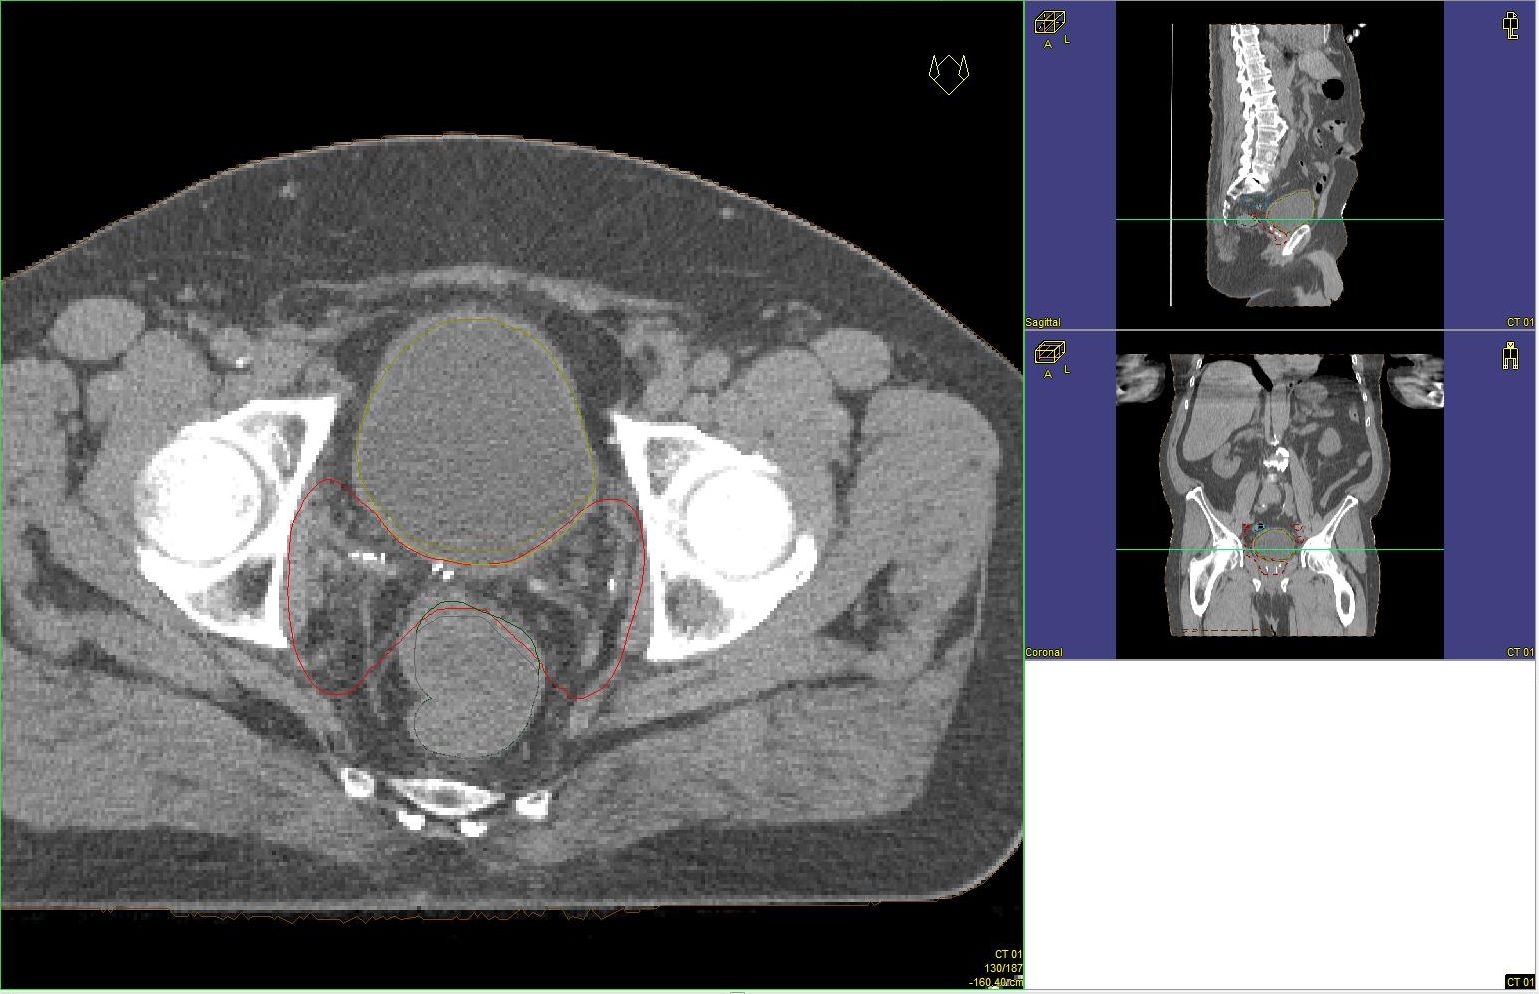

Prostata-Ca: Zielvolumen der postoperativen Radiotherapie

Beispiel: postoperative RT